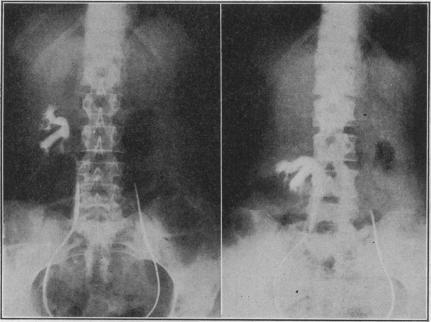

Dickson A R

Cal West Med. 1931 Sep;35(3):204-7.